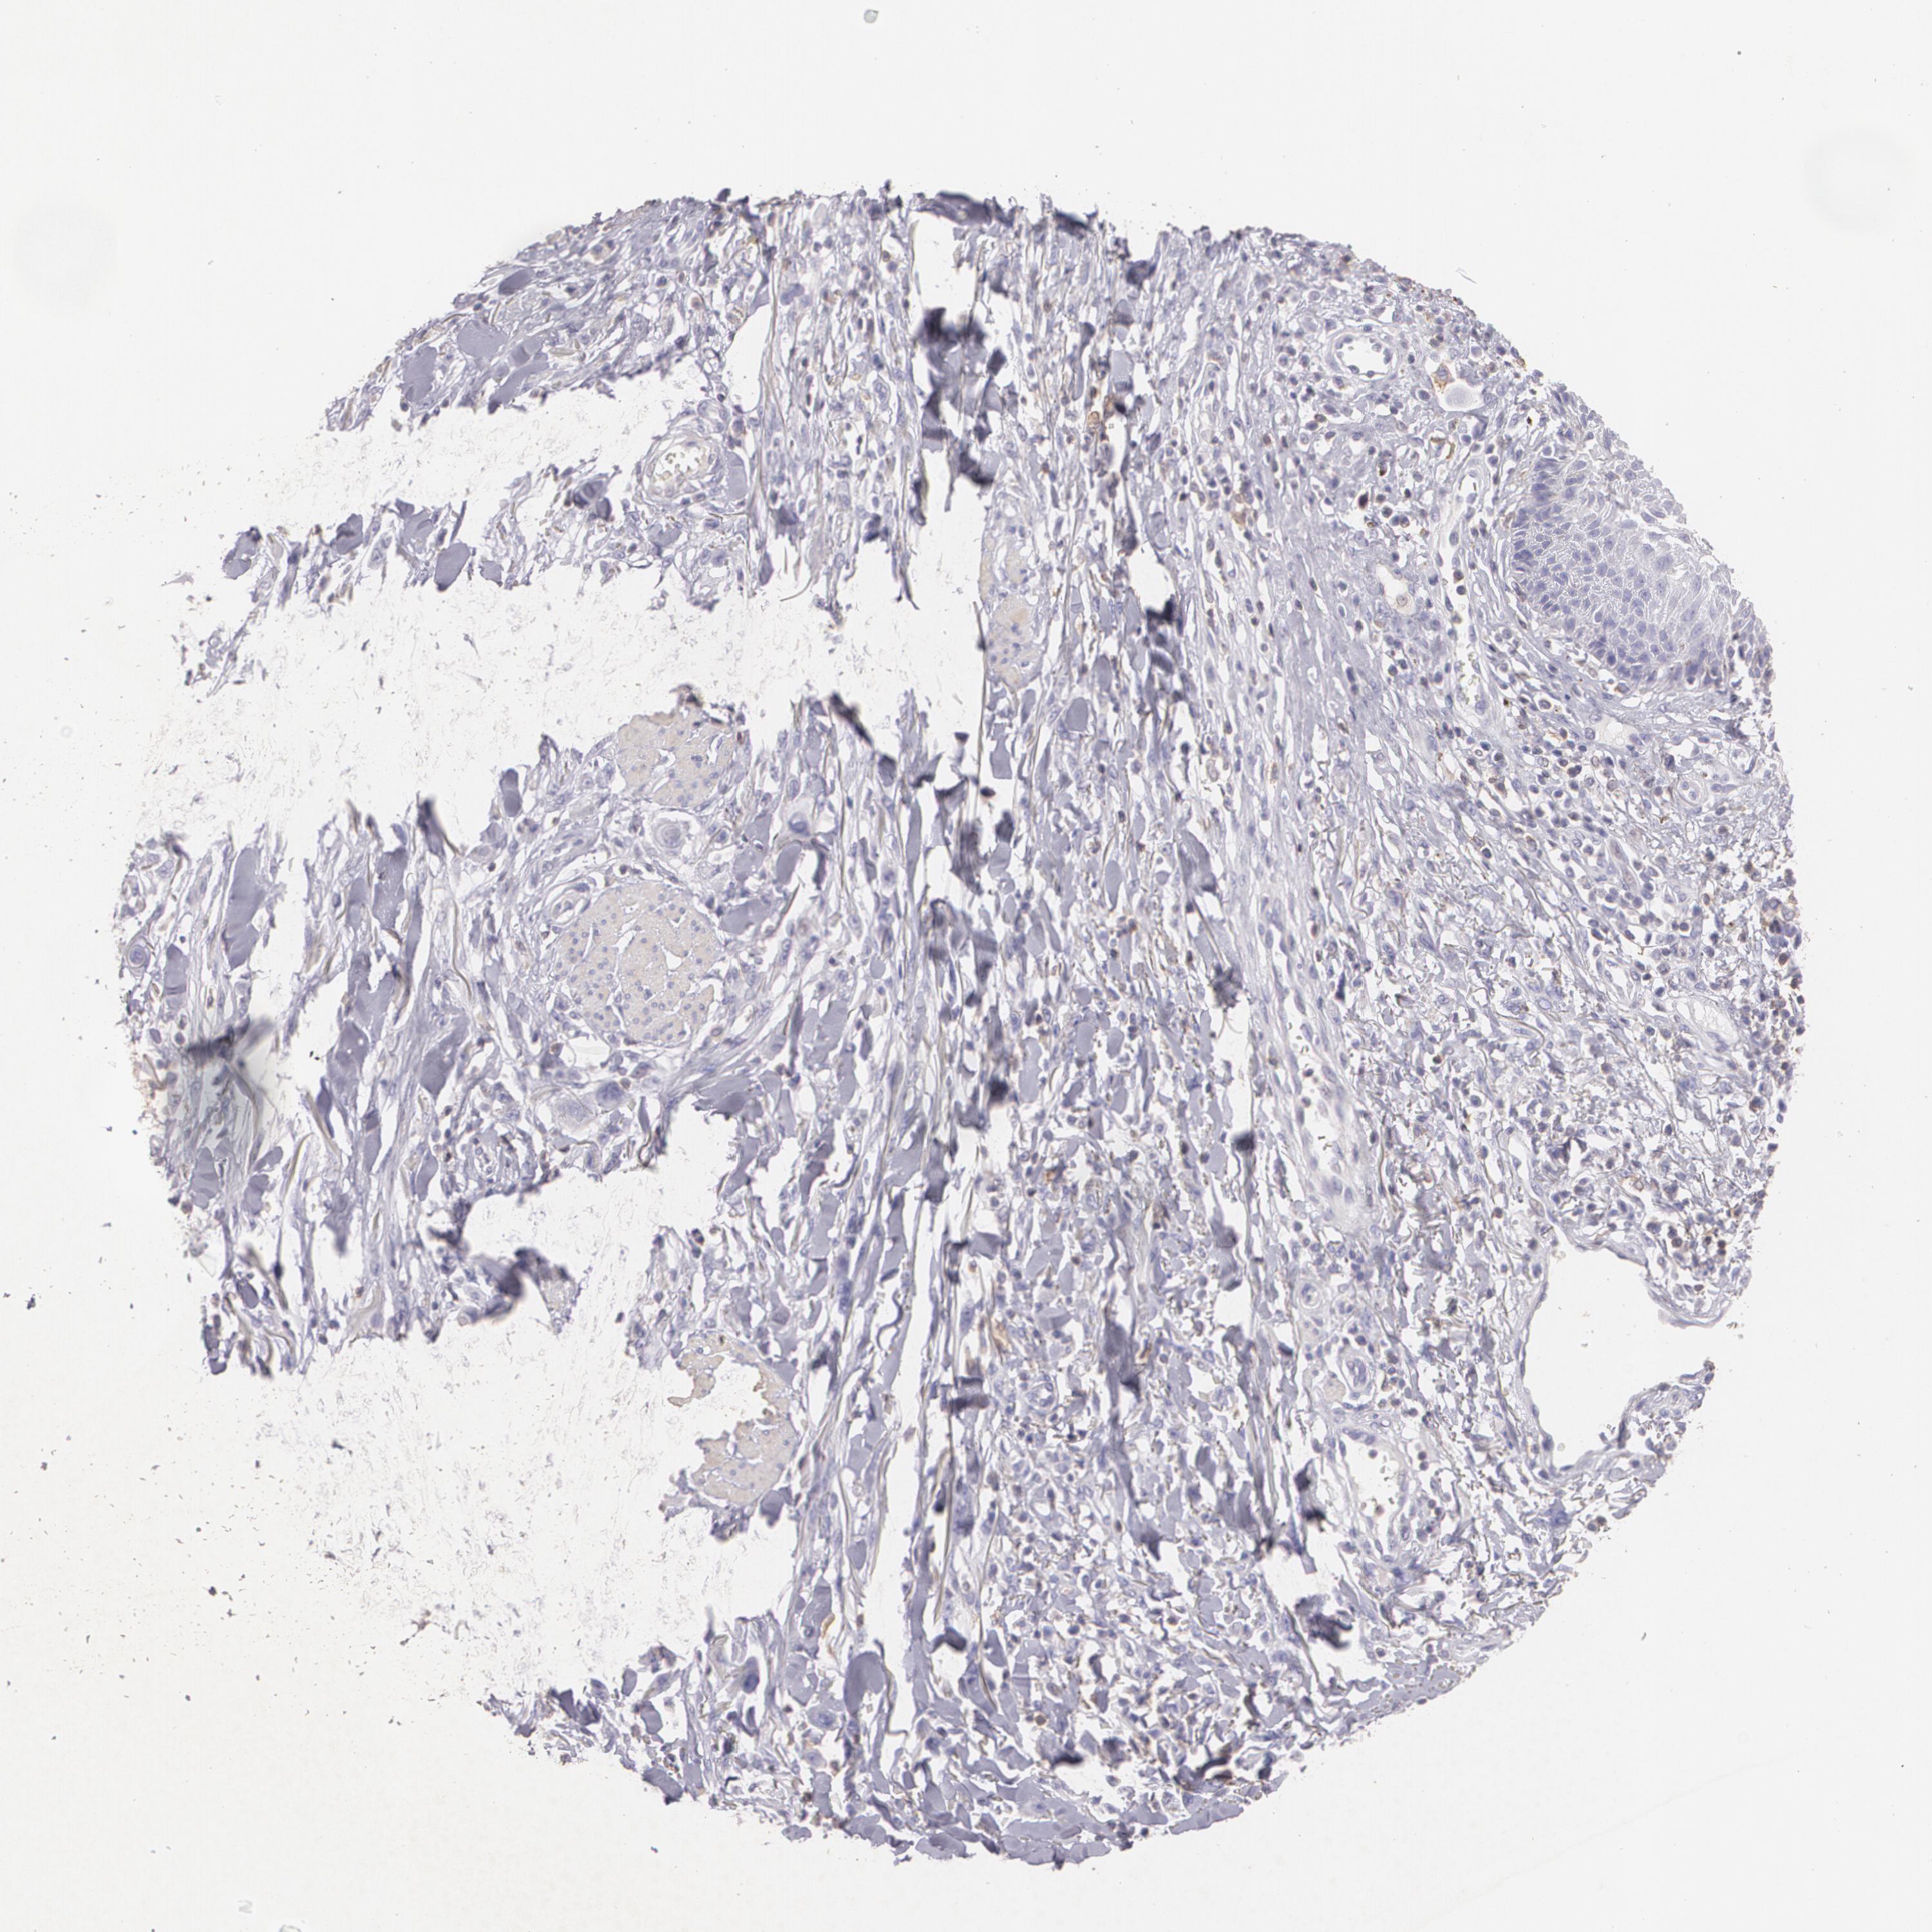

SKIN CANCER - Protein expressioni

A mouse-over function shows sample information and annotation data. Click on an image to view it in a full screen mode. Samples can be filtered based on level of antibody staining by selecting one or several of the following categories: high, medium, low and not detected. The assay and annotation is described here.

Each image is clickable and will lead to virtual microscopy that enables deeper exploration of all samples and also displays staining intensity scores, fraction scores and subcellular localization as well as patient and tissue information for each sample.

Antibody CAB002441

Squamous cell carcinoma, NOS